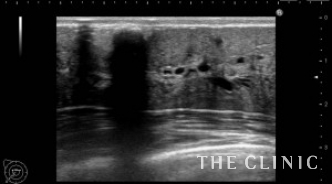

この方は、8年前に他院で脂肪による豊胸術を受けられました。その後、乳がん検診で多発する石灰化したしこりを指摘されたため、当院を受診されました。超音波検査では、右に7個、左に5個の石灰化したしこりを認めました。

石灰化したしこりは広範囲にあったため、乳輪切開という方法で摘出しました。